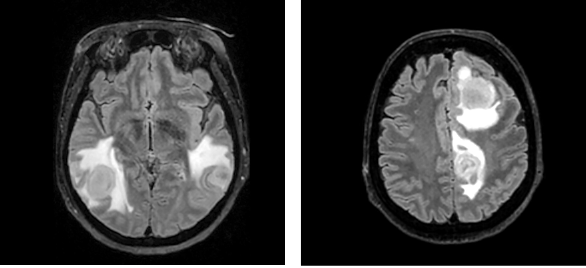

During elbow surgery, the patient experienced respiratory insufficiency, necessitating transfer to the Intensive Care Unit (ICU). Once stabilized, she was moved to the Neurology Department. Subsequent deterioration during a routine morning examination included nausea, diaphoresis, elevated blood pressure (220/90 mmHg), and tachycardia (heart rate 100 bpm). The worsening respiratory insufficiency led to her transfer to the Neurosurgical ICU and subsequent intubation. Despite normal laboratory findings, a chest CT revealed inflammatory infiltration and hypoventilation, but an infection was initially ruled out, precluding antibiotic administration. However, a repeated bronchoscopy culture isolated Proteus Mirabilis, sensitive to Cefuroxime, leading to a diagnosis of respiratory muscle weakness potentially related to myasthenia, and subsequent plasmapheresis was initiated. After extubation and initial stabilization, MRI revealed brain lesions to be consistently recognized as abscesses (Fig. 2).

Fig. 2. T2-weighted brain MRI sequence shows multiple hyperintense foci, most consistent with abscesses. The ventricular system is of normal width, the left lateral ventricle is compressed due to the lesion on the left P. The midline structures minimally prolapse to the right

The patient’s condition deteriorated during transportation, requiring re-intubation. Neurosurgical intervention was not considered viable. Consequently, the antibiotic regimen was expanded to include Ceftriaxone, Vancomycin, Metronidazole, and Sulfamethoxazole-Trimethoprim, targeting a broader spectrum of pathogens potentially responsible for brain abscesses. Despite plans to conduct diagnostic tests for HIV, syphilis, toxoplasmosis, and Listeria from the abscess aspirates, the patient’s condition rapidly deteriorated, becoming critically unstable. This acute decline was marked by severe respiratory insufficiency and profound bradycardia, necessitating immediate cardiopulmonary resuscitation (CPR) and the urgent administration of Atropine. Finally, due to prolonged intubation, it was decided to form a tracheostomy. Subsequent MRI showed a reduction in the abscess size (Fig. 3), and the patient was transferred to the Neurology Department for continued care.

Fig. 3. Brain MRI, T2W sequence. MRI showed positive dynamics – brain abscesses have decreased in size. The surrounding perifocal edema has also decreased dynamically. The ventricular system is no longer deformed, and there is no displacement of midline structures. There are no signs of ventriculitis or new intracranial abscesses in the dynamics